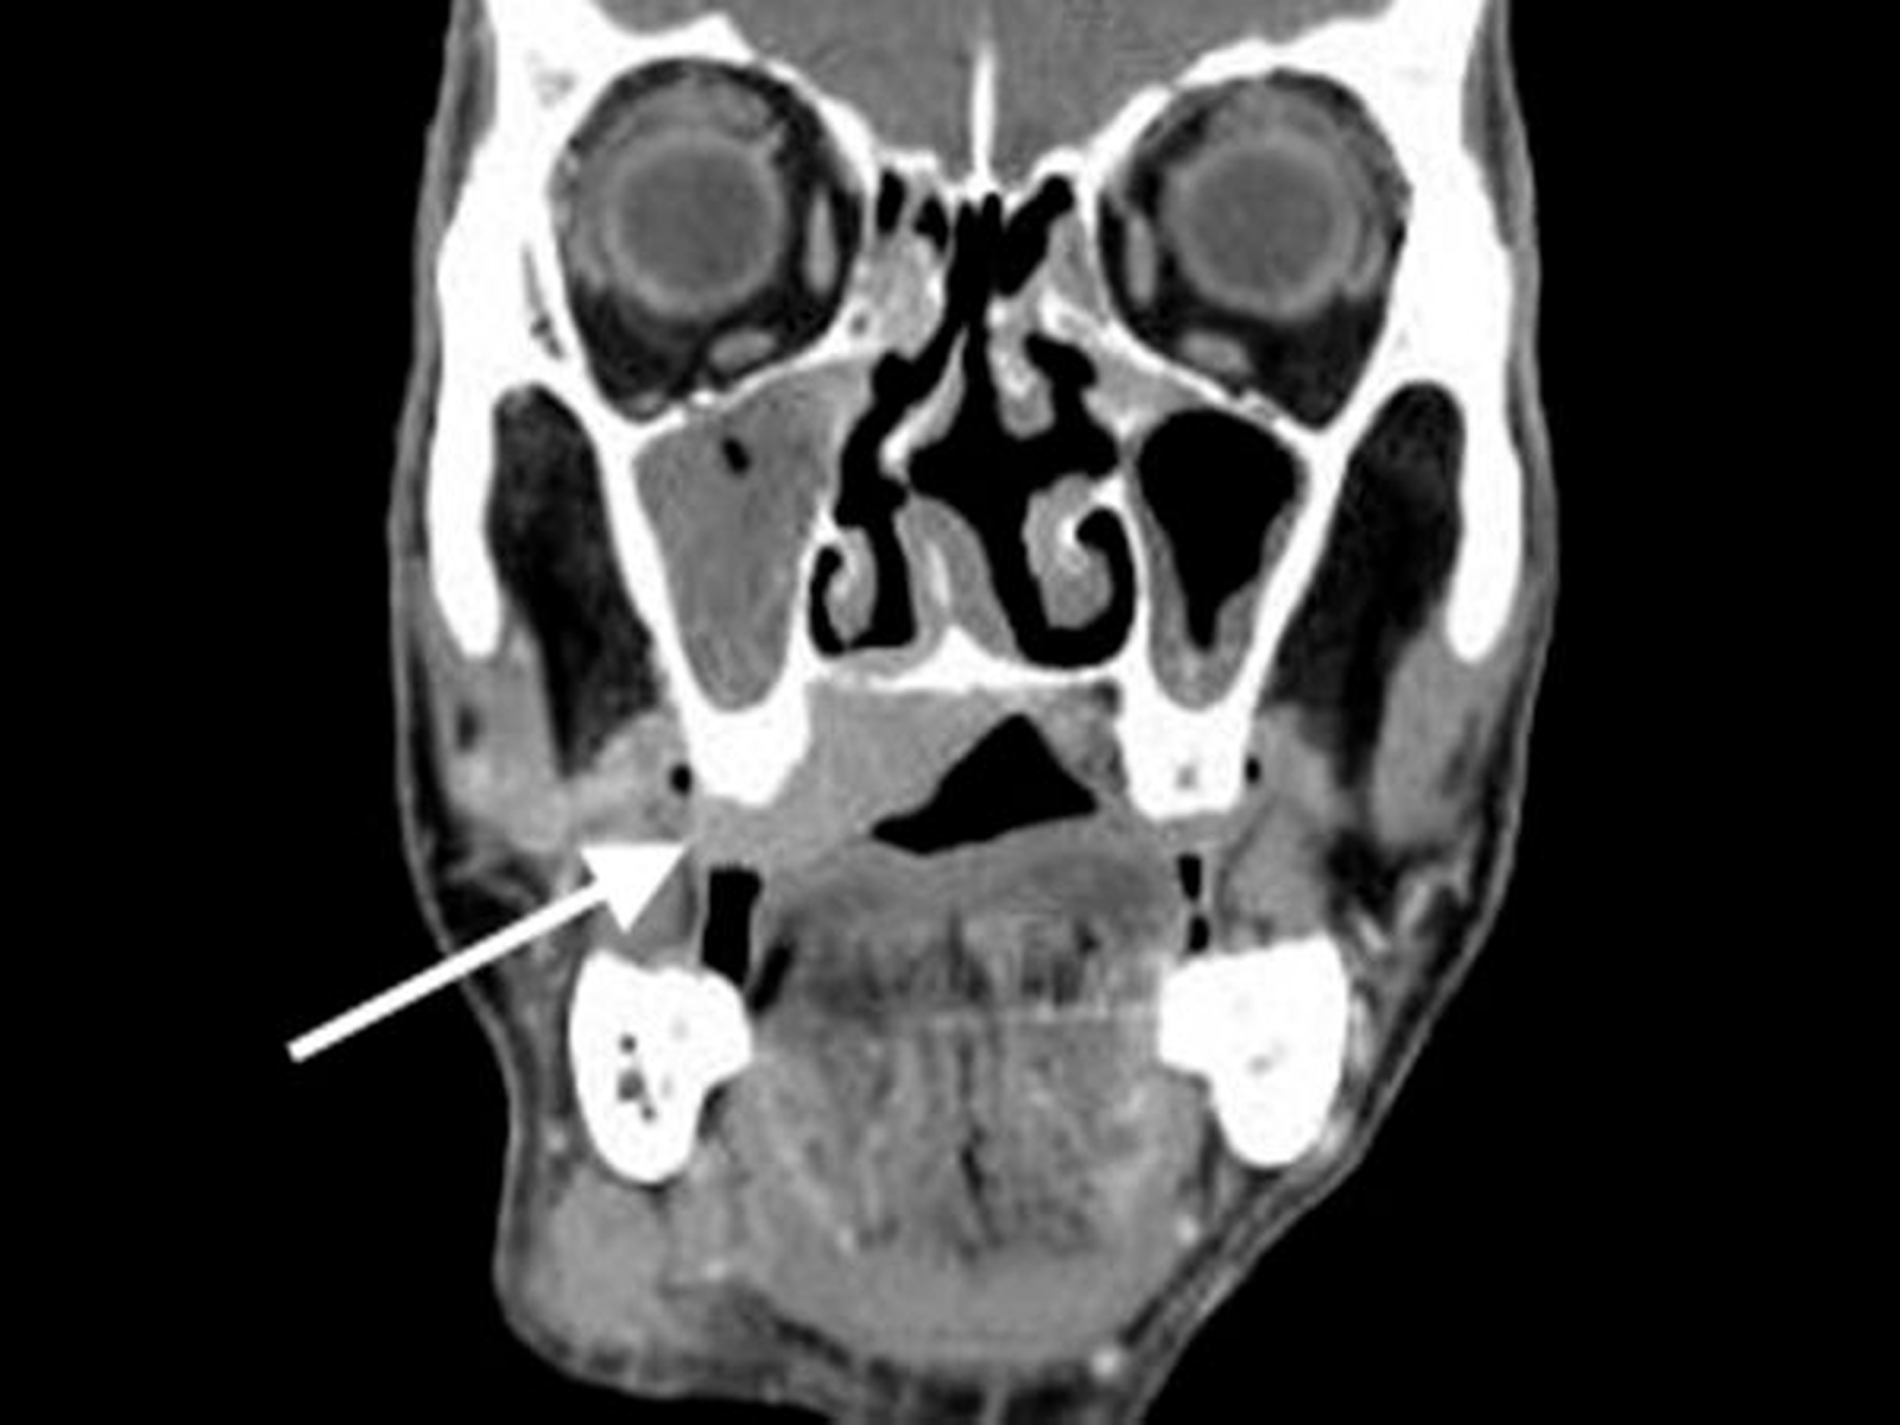

Bei hochgradigem Verdacht auf ein Malignom wurde der Patient daraufhin stationär zum Staging aufgenommen. In der Labordiagnostik fanden sich unauffällige Routine-Parameter in der klinischen Chemie, dem Blutbild, der Gerinnung und Serologie (Hepatitis B und C sowie HIV), lediglich die Blutkörper-Senkung war mit 45 mm/Std erhöht (Referenz <20 mm/Std). In der durchgeführten Kopf-Hals-CT fand sich eine tumoröse Raumforderung des Oberkiefers und Gaumens mit einer Größe von 37mm x 22mm mit Mittellinienüberschreitung und Einbeziehung des Alveolarkamms (Abbildung 3a).